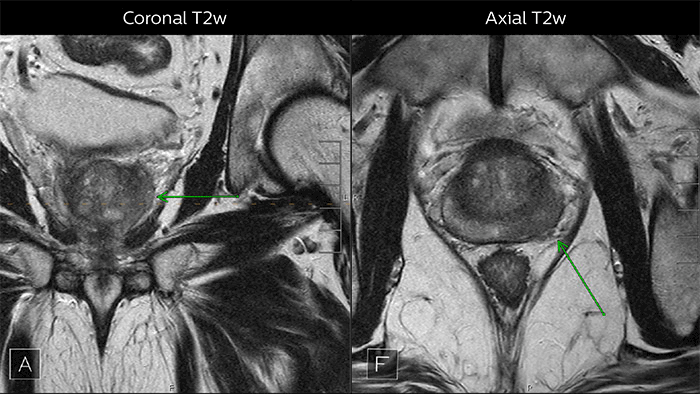

Predictable MRI patterns help identify suspicious lesions

Depending upon the Gleason score and prior therapies, prostate carcinoma has a certain predictable pattern on multiparametric MRI, according to Dr. Steiner. “In general, lesions in the peripheral zone have decreased T2-weighted signal and are relatively focal,” he says. “In the transitional zone, these lesions are more difficult to evaluate on T1 and T2, but are generally non-encapsulated.”

“We also look at diffusion-weighted images and the ADC map. Prostate neoplasms generally have diffusion restriction, so they are bright on diffusion-weighted imaging and dark on an ADC map, which is one of the most important characteristics of neoplasms.”

Multiparametric MRI of a classic peripheral zone lesion Dr. Steiner describes this case: “For lesions in the peripheral zone of the prostate, the DWI (diffusion weighted imaging) and ADC map are most helpful for diagnosis. In this case, the DWI shows a very bright signal, which indicates diffusion restriction. The arcuate area with significant signal drop out (arrow) on the ADC map is recognized as highly suspect for tumor. On the axial T2-weighted image the capsule contour looks a little irregular (arrow), which we interpret as capsular disruption, and I usually give a measurement: this lesion shows larger than 1.5 cm capsular disruption. I don’t see any signs of lymphadenopathy, but interpret this lesion as PI-RADS 5. The hypervascular flow pattern in the bottom images adds to the diagnostic confidence.”